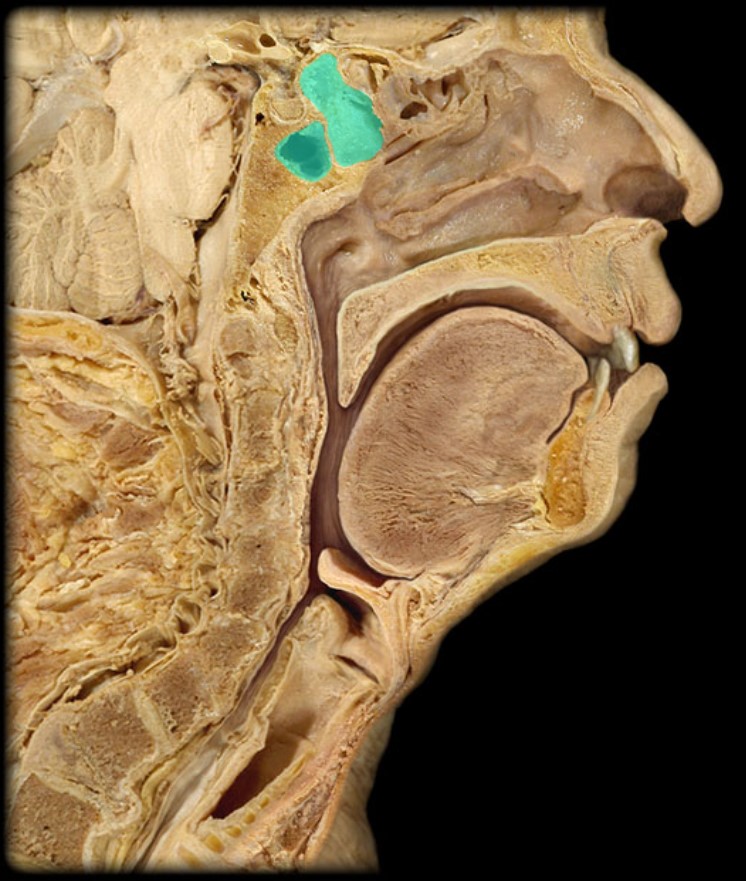

Thyroid Gland

Atlas

Vertebral Artery

Nasal Septum

Pharyngeal Tonsil

Auditory Hiatus

Torus Tubarius

Sphenoid Sinus

Inferior Nasal Concha

Middle Nasal Concha

Superior Nasal Concha